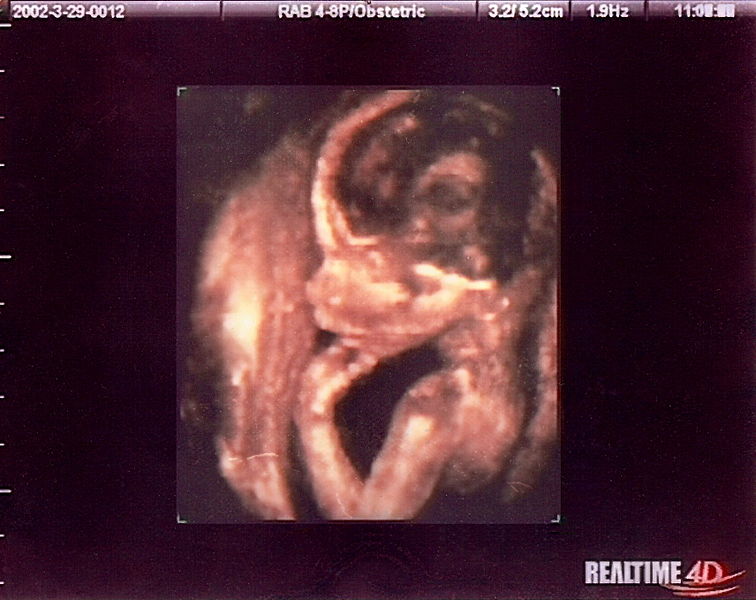

might be. They are invented in darkness —

under cloak of skin — and, for the better

part of a year, are a swelling

of dreaming about a creature who is

almost but not quite. It is a way of

imagining the soul of a person you

are making but have not made.

The name is the first way you see

the baby: their title, the syllables

that conjure a shape from the lantern.